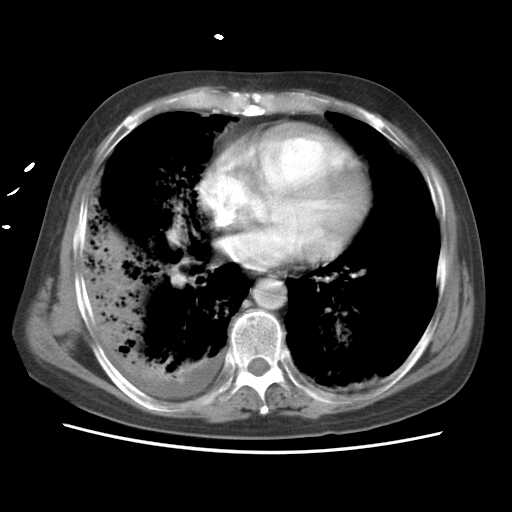

2008.8.17ct

病变从8.11-8.17明显改变,增多,以蜂窝状改变为主,类蜂窝肺,似弥漫性肺泡癌,但是病变进展太快,不符合弥漫性细支气管肺泡癌。因此考虑为特殊微生物感染,多以霉菌类常见,建议细菌微生物学检查。

疑点二:影象表现怪异,大片阴影内见多发筛孔征,如何解释.

结合临床慢支炎肺气肿,肺心病病史,三次胸片观察可见病情发展变化迅速,病情凶险,考虑多重感染伴ards.